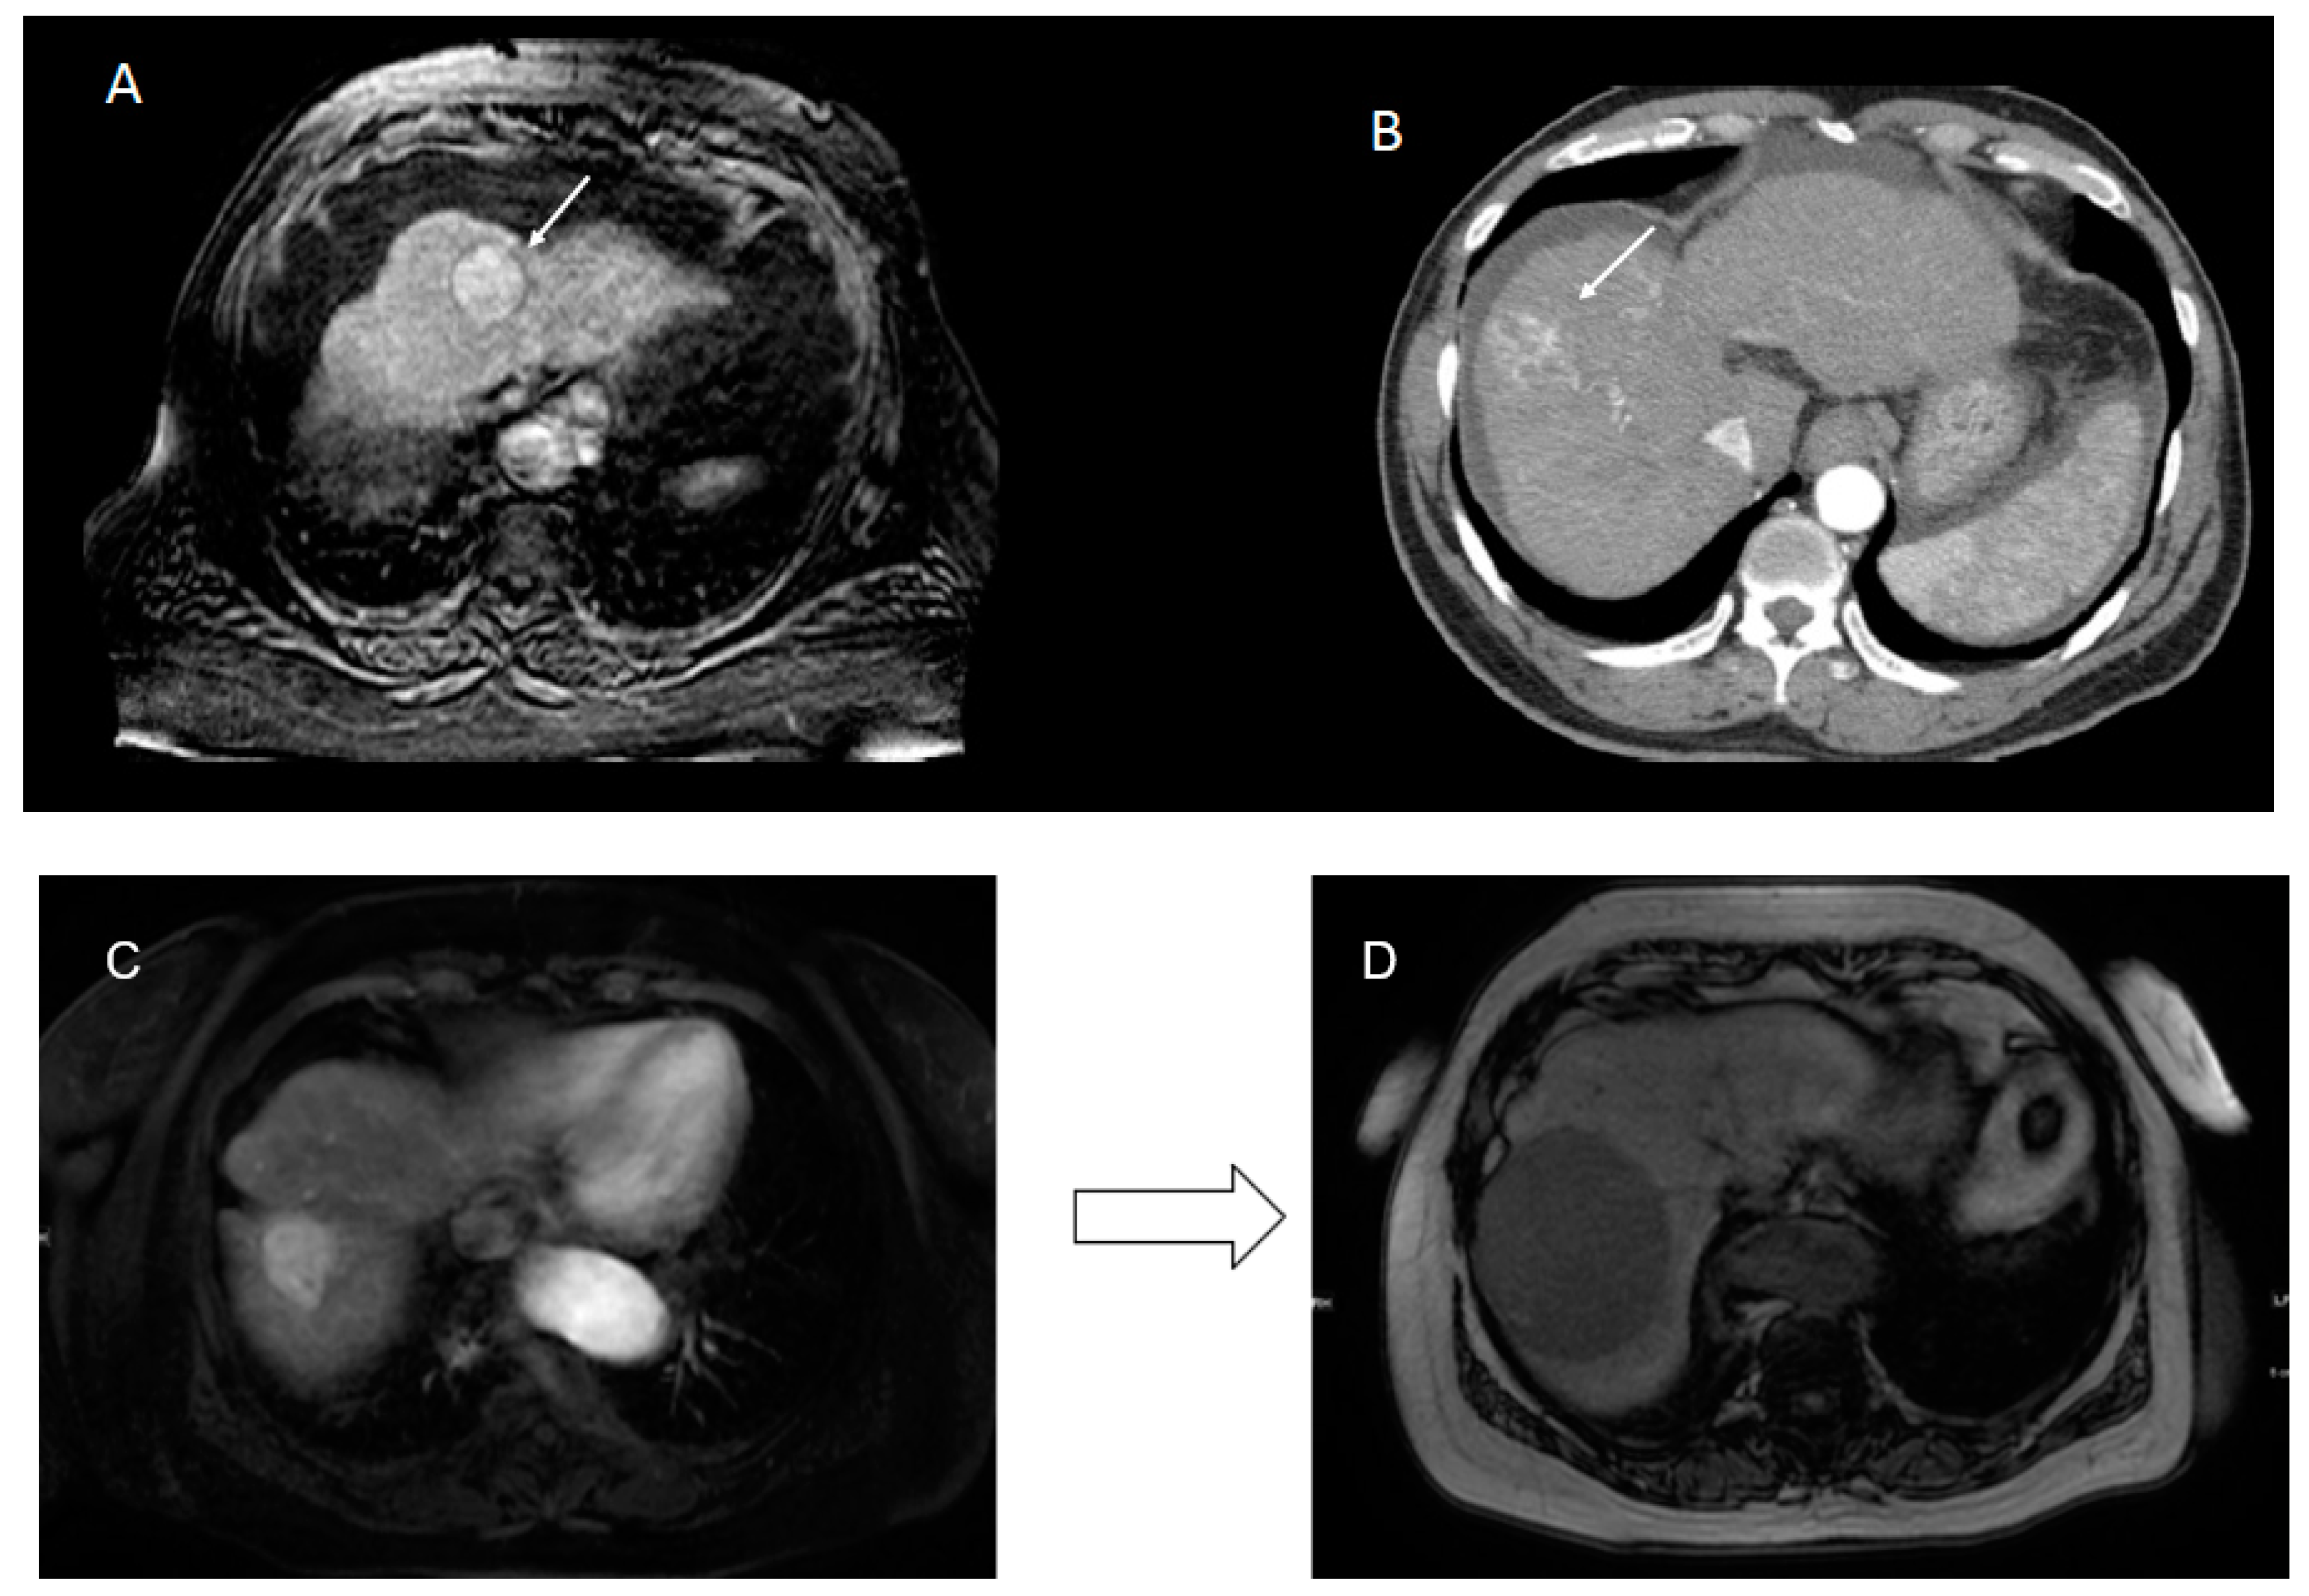

3.1. Cohort and Visual Features